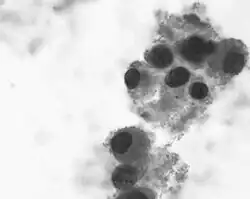

Obraz histologiczny guza jest różnorodny. Stwierdza się obecność pęczków włókienkowych z silną desmoplazją podścieliska, przypominającą obraz nerwiakowłókniaka. Opisuje się także "wiatraczkowe" układy komórek, przypominające układy komórkowe w preparatach dermatofibroma. Cechą charakterystyczną DIG jest obecność komórek neuronalnych, przypominających komórki zwojowe. W DCAI nie ma tych komórek, poza tym obraz mikroskopowy jest identyczny.